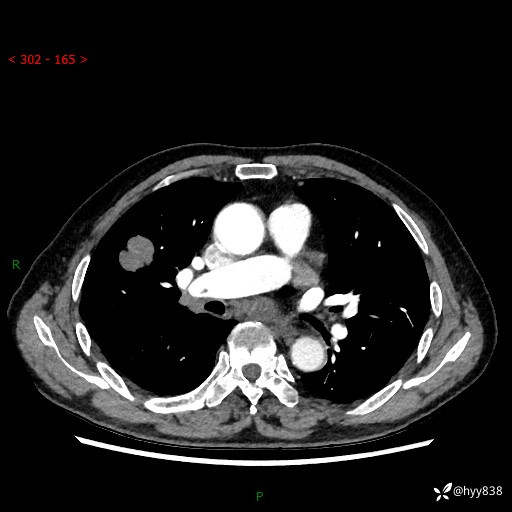

69岁/男,间断咳嗽伴气促、下肢水肿。临床拟诊肺栓,偶发肺均质强化结节--结果公布

【患者信息】:69岁/男

【主诉】:间断咳嗽伴气促、下肢水肿2周

【现病史及既往史】:患者2周来无明显诱因出现咳嗽,咳少量白痰,不易咳出,伴有气促,呈间断发作,症状与活动费力相关,以夜间为甚,不能平躺入睡,偶有憋醒,无胸闷胸痛、无发热、无头晕、头痛等不适,伴有双下肢中度水肿,就诊于当地县人民医院门诊,完善相关检查提示:左下肢深静脉血栓形成,未予以特殊处理,今患者为求进一步诊治来我院就诊,拟“心衰”收入我科。 起病以来,患者精神、饮食、睡眠可,大小便如常,体力明显下降,体重未见明显减轻。

【检查】:胸部CT增强